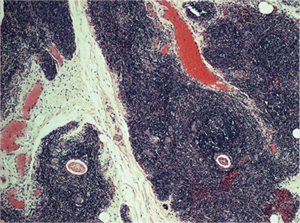

Preoperative stage, according to MGFA classification, was stage I in 2 patients (15.4%), II in 4 (30.8%), III in 3 (23%) and stage IV in 1 patient (7.7%). The mean operation time was of 164 minutes (range, 45–275 minutes) with minimal blood loss. One patient had a myasthenic crisis after surgery, resolved with intravenous immunoglobulins. The length of hospitalization was 3 days (range, 2–5 days). Final histology demonstrated thymic hyperplasia in 8 cases (61.5%), Hassall’s corpuscles in 2 cases (15.4%) (Figure 3), adipose involution in 1 case (7.7%) and a B2 thymoma in 1 case (7.7%). The pulmonary nodule demonstrated as normal lung tissue.